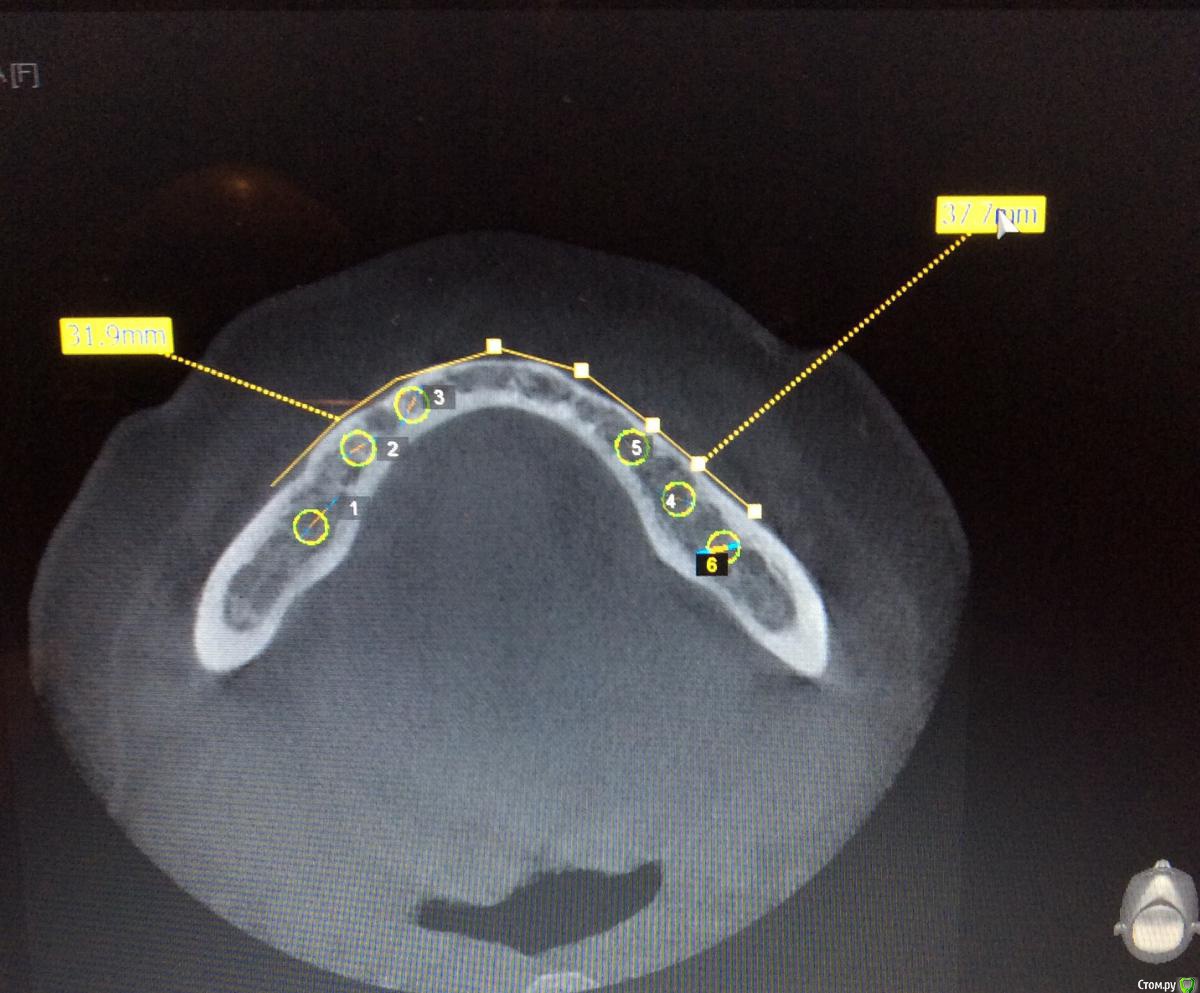

Neilrus Опубликовано 26 мая, 2015 Поделиться Опубликовано 26 мая, 2015 Здравствуйте, подскажите как быть в моей ситауции. Такого объема лечение я еще не выполнял. Беззубая н/ч. Планируем несъемное, "все на 6". Спланировал шаблон по кт на 6 имлантатов, жду его приезда из Москвы. Имплантаты mis m4. 3,8*11,5 и 10.0Планируется так же костная пластика одновременно в районе постановки имплантатов (где-то расщепление, где-то досыпка)Вот отсюда и вопрос, если мы ей пластику делаем, как сдать ей её же временный съемный протез на котором мы ей сейчас прикус зафиксировали? не держать же ее 2 месяца без протеза. У меня вариант в голове только с временными микроимплантатами с шариками Mis, диаметром 3.0 их я смогу и без шаблона поставить.А) Ни разу не делал такой конструкции, так возможно? Б) Двух микроимплантатов в позиции клыков или четверок достаточно? Через какое время можно их нагрузить? В) Ничего что они будут стоять либо между двумя пластиками, либо вообще сквозь ламину (или evolution).Г) Есть какие-нибудь более правильные варианты? Ни один из поставленных имплантатов нагружать не хочу, формики тоже при условии пластики ставить не рискну, опыт еще не тот.Д) профиль челюсти изменится, станет шире, в протезе, если его сдаем, нужно спилить базис немного и сделать перебазировку эластичной пластмассой? Спасибо всем за советы заранее)) сорри если что не так или если повторил тему, не нашел в форуме ответ. Ссылка на комментарий

Neilrus Опубликовано 29 мая, 2015 Автор Поделиться Опубликовано 29 мая, 2015 Сделайте срезы планнинга по каждому имплантату. Там будет понятно.46з45з44з 34з35з36з Может можно воссатновить на двух микроимпл только от клыка до клыка чтобы губа не западала и для сохранения высоты? Ссылка на комментарий